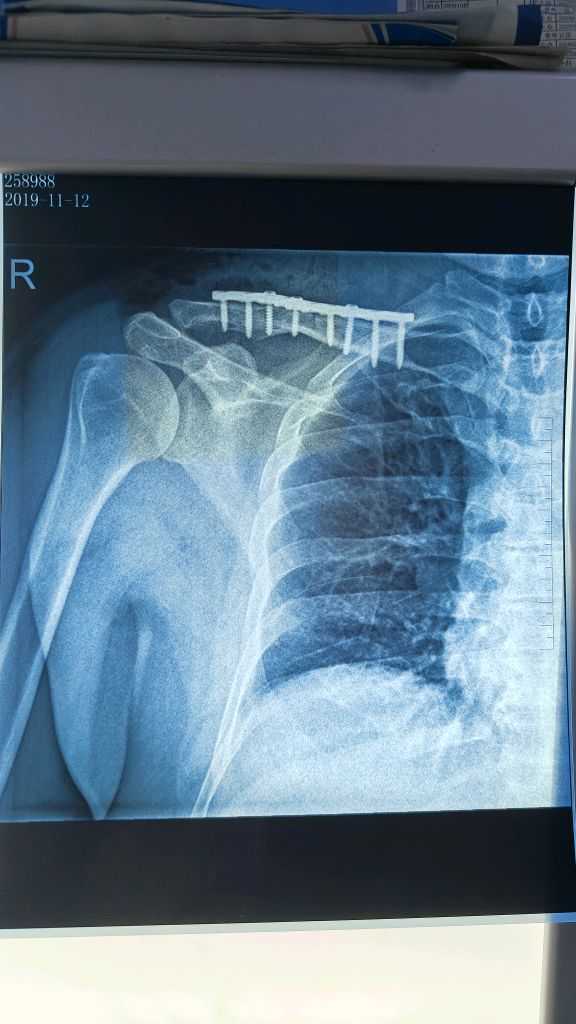

很多患者在复查X片时看到骨折处依旧“黑乎乎一片”,心里立马咯噔一下:“一个月了,怎么还没长骨痂?是不是不愈合了?”这种焦虑非常普遍。从患者角度来说,等待骨痂显影的过程,本身就像是一场煎熬,每天盯着患肢,生怕出现什么“失败的信号”。

答案并不绝对。临床上,大部分长得快的骨折,比如儿童,往往两三周就能看到毛糙的影子,而成年人通常需要四到六周才能显影。骨头不是流水线,愈合速度受很多因素影响,年龄、骨折部位、骨折类型、血供情况、营养和固定方式,都能左右进度。有些髋部或胫骨远端的骨折,血液循环差,骨痂本来就起步慢。

如果影像上完全没动静,我们会警惕以下几种情况:一是固定不牢,骨折端微动过多,骨痂还没来得及长就被“搅掉”;二是局部血供差,比如开放性骨折或软组织损伤严重,导致“养分运不过去”;三是全身因素,包括营养不足、长期抽烟喝酒、内分泌紊乱,甚至合并糖尿病等。还有一种常被忽略的情况,就是药物影响,比如长期吃糖皮质激素,也可能让骨痂迟迟不长。

在临床上,一个月没有骨痂,并不等于骨头一定不愈合。多数情况下,医生会建议再观察2-3周,并同时检查患者的全身情况。影像学上没有骨痂,不代表显微层面没动静,有时骨折周围已经有纤维性连接,只是X片暂时看不清楚。如果确实怀疑愈合迟缓,医生可能会调整固定方式,增加支撑,或者考虑促进骨痂形成的治疗,比如低强度脉冲超声、磁场刺激等。部分患者会被建议增加蛋白质和钙磷摄入,当然,补钙不是万能的,关键还是整体代谢环境。